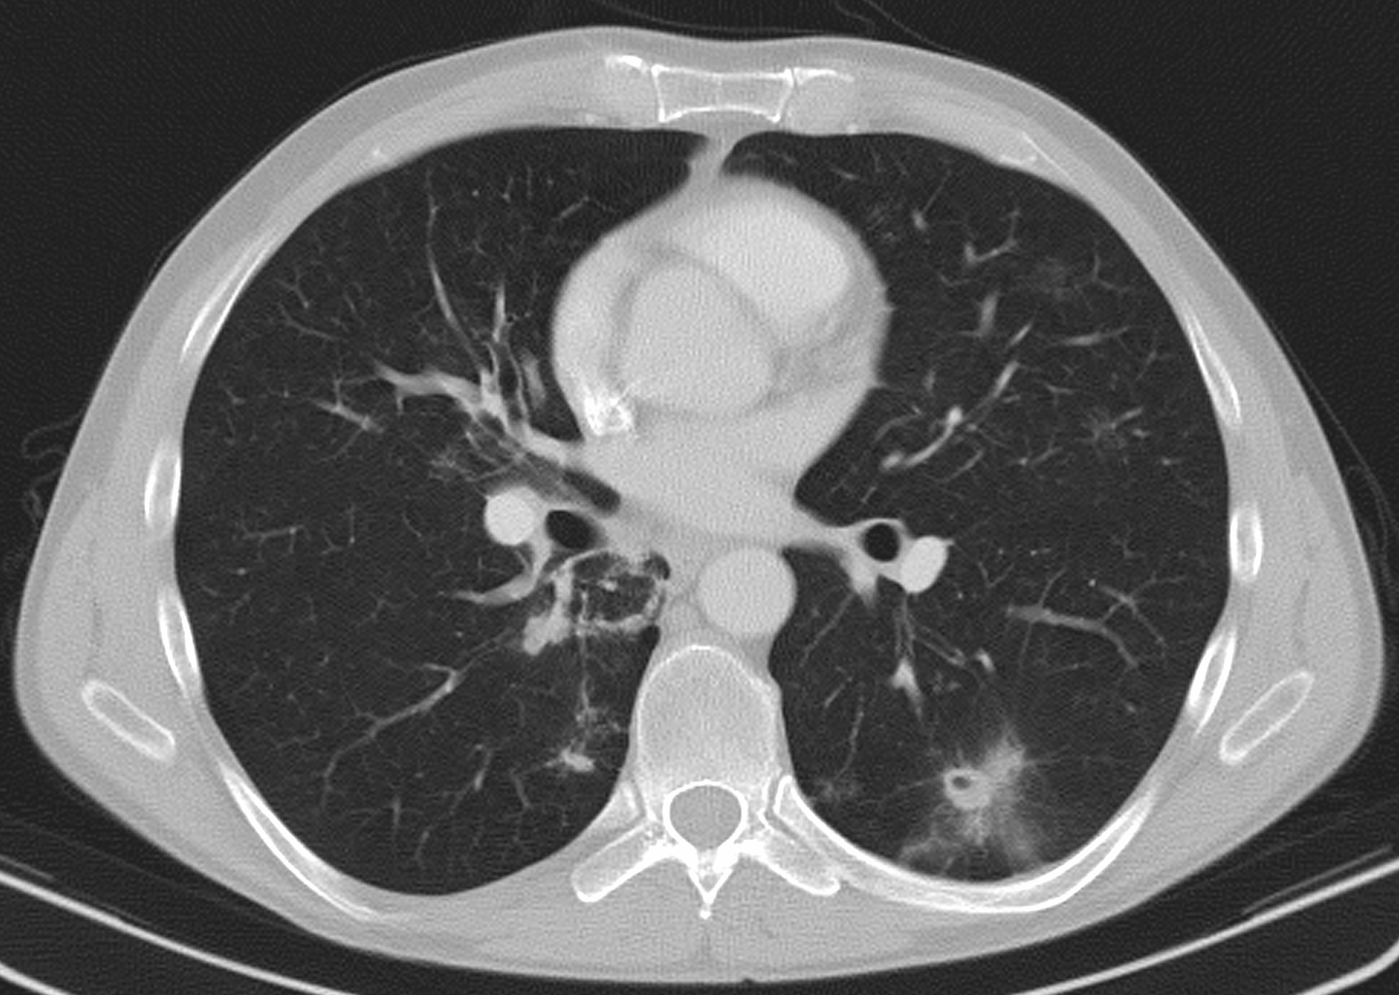

3b: Multiple lung metastasis, CT lung window (axial, coronal reformat)

Image

3c, coronal reformat

70 year old man, colon tumor.

Radiograph: Bilateral extensive, confluating patchy-nodular shadowing with diffuse reticular pattern. The diaphragm contour is partially blurry bilaterally: lymphangiosis carcinomatosa.

CT: Numerous 1-6 cm round and irregular, lobulated-spiculated contrast enhancing lesions in both lungs, everywhere sporadically.